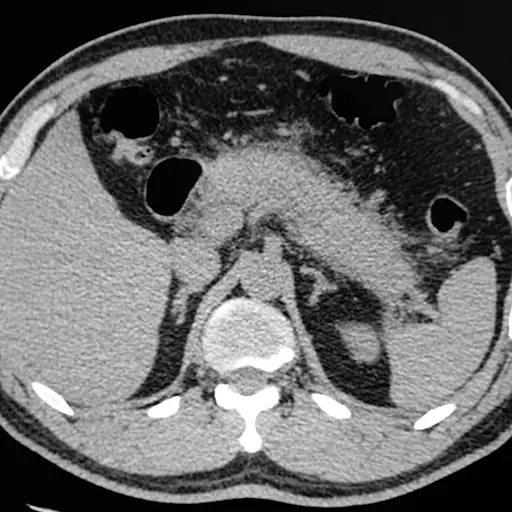

甘油三酯和你的胰腺

如果你有非常高的甘油三酯-超过500毫克/ dl -你的胰腺会受到严重的打击。胰腺是一种帮助将食物转化为体内燃料的器官。甘油三酯水平如此之高的人很有可能患上一种叫做急性胰腺炎的严重炎症。

“这是一个非常危险的情况,”夏皮罗博士说。“除了非常不舒服,非常严重的急性胰腺炎可能是一个致命事件。胰腺炎的多重复发可以杀死足够的胰腺β-胰岛细胞 - 产生胰岛素的胰腺炎 - 糖尿病发展。“没有那些β-胰岛细胞,你不能产生你身体需要管理血糖的胰岛素。与饮食和运动的温和升高的TG水平相比,严重升高的TG具有胰腺炎相对罕见。